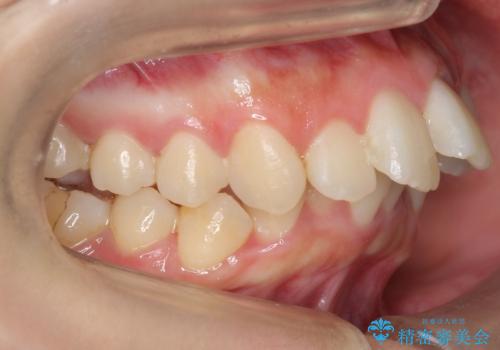

左上の小臼歯が込み合っており、虫歯治療が厳しい状態でした。

矯正治療をおすすめし、ちょうど虫歯がひどい歯は抜歯して前歯を下げました。

下顎の大臼歯が前に倒れこんでいたため、矯正用ミニスクリューで後ろに起こしています。